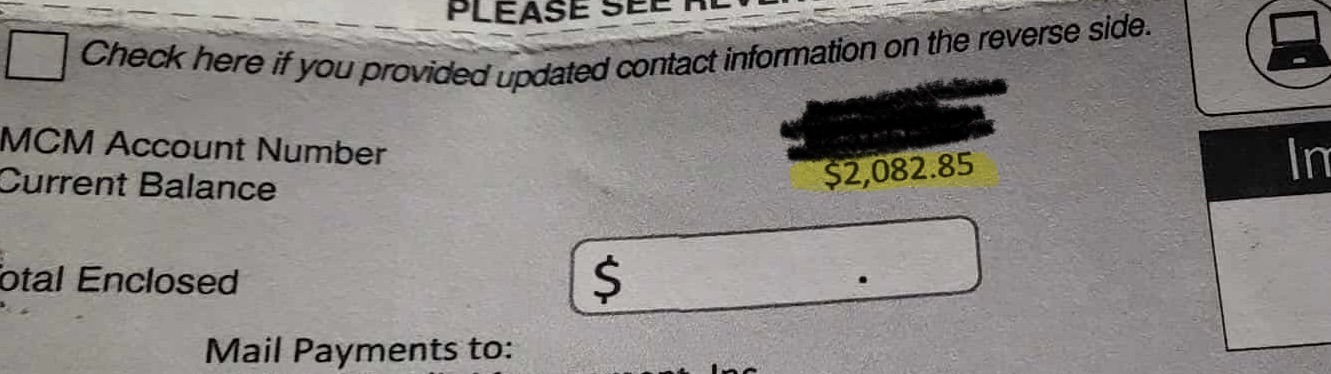

Hi I'm raising money for my friend and former coworker Melissa Brown, a hard worker, talented human being, and loving mother who has been going through a lot this last year. From neck surgery (cervical anterior arthroplasty total disc single level) to diagnoses such as P.O.T.S., E.D.S., M.C.A.S., sleep apnea, hernia, P.C.O.S. and more, there are countless medical bills from appointments, tests, hospitalizations, and medications. The cherry on top? Her health has recently declined to the point she can no longer work unless it's from home.

Let's all chip in to support Melissa and her two young sons while she searches for a work from home job amidst these medical crises! Every bit, even just $5 helps feed her family, pay for medication, keep a roof over her head while life sorts itself out. Thank you for reading and stay blessed.